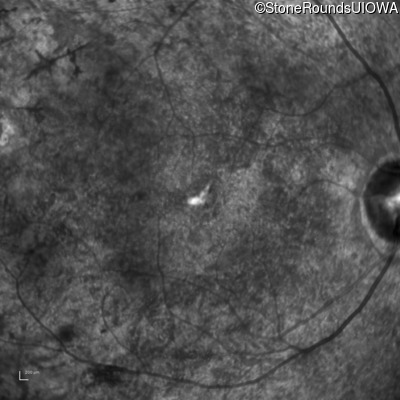

AR Retinitis Pigmentosa (IA1aiii)

Age at visit: 43 years

This 43 year old woman has had poor peripheral vision and poor night vision since childhood. She recalls sometimes having to back-up to find something she dropped on the floor. She first came to ophthalmologic attention at age 10 when there was concern for cataract formation associated with high doses of oral steroids she was receiving for asthma.

AR Retinitis Pigmentosa TMEM216 -69u G>T -69u G>T AR